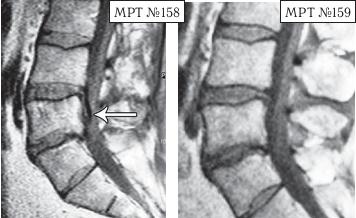

На МРТ № 158 наблюдается состояние поясничного отдела позвоночника после хирургической операции в сегменте LV—SI и образовавшаяся секвестрированная грыжа межпозвонкового диска в сегменте LIV-LV с каудальной (вниз) миграцией секвестра вдоль тела позвонка LV, сужение просвета спинномозгового канала (стеноз). На МРТ № 159 — состояние поясничного отдела позвоночника после лечения методом вертеброревитологии: отсутствие грыжи межпозвонкового диска в сегменте LIV-LV, ширина в данном участке спинномозгового канала восстановлена до естественной его нормы. Конечно, с позиции наблюдателя, неискушённого в тонкостях вариабельности различных коварных патологий, МРТ № 158, после вышерассмотренных грыж значительных размеров, мягко говоря, не впечатляет. Но специалисты, надеюсь, прекрасно понимают, насколько это сложный случай, даже по сравнению с эпизодами наличия больших секвестрированных грыж. Думаю, что подробности этого случая будет интересно узнать также и вам, уважаемый читатель. Дело в том, что у данного пациента по природе довольно суженный спинномозговой канал, то есть, говоря медицинским языком, наблюдается стеноз спинномозгового канала первого типа (врождённый). А здесь ещё и такое осложнение: длительная локализация секвестра грыжи вследствие постоянных воспалительных процессов вызвала гипертрофию задней продольной связки и своеобразно «подпаялась» к ней. Таким образом, подобная патология (секвестр) значительно усугубила ситуацию: практически на 50 % дополнительно сузила и так изначально врождённый узкий спинномозговой канал. Естественно, у пациента появились боли и слабость в обеих ногах. |